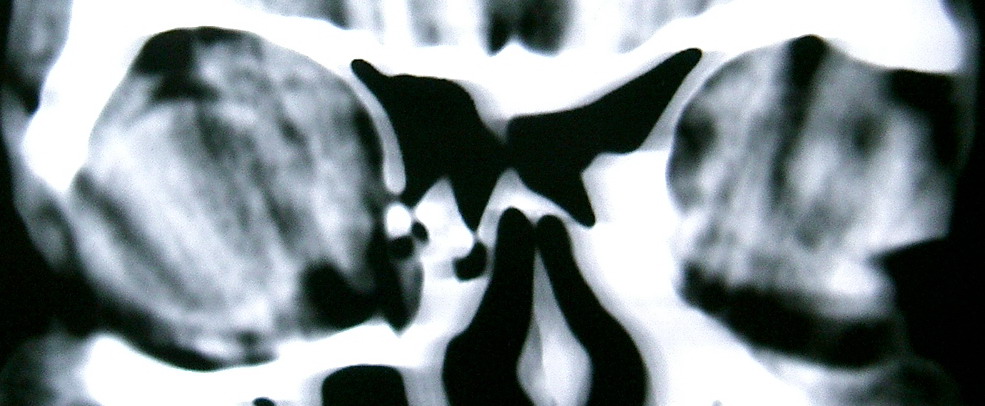

眼眶冠扫,平扫CT:

左眼球内上方可见不规则软组织块影,大小约2.5*1.0CM,与邻近组织分界不清,相邻之内直肌、上直肌增粗,眼环正常,眶壁骨质无破坏,左上颌窦底部可见粘膜增厚,其余副鼻窦未见异常。

IMP:1,左眼眶肿物;2,左上颌窦炎